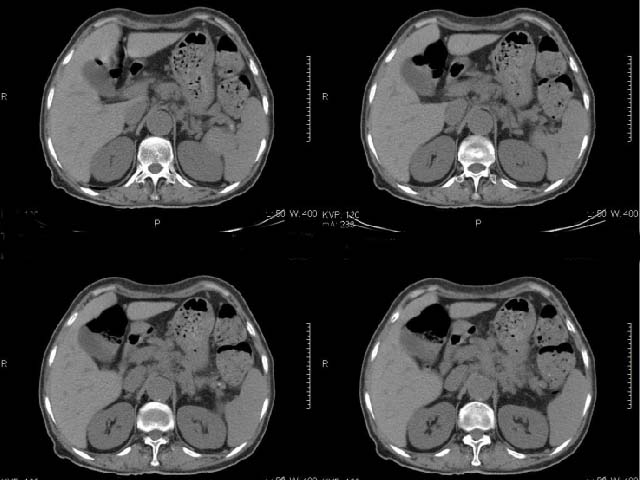

女,69岁,浑身乏力,腹泻半年余,无腹疼,排泄物中含有脂肪球,抗炎治疗一周仍不缓解,来我院检查发现明显低钾血症,给予补钾(氯化钾)一周后,血钾恢复正常,经化验检查,尿钾持续明显高于正常,临床考虑患者不仅消化道失钾,还伴有泌尿系统失钾,故进行ct增强检查看肾上腺是否有病变。ct表现为胰腺肥大,而且体尾部强化较弱,明显呈稍低密度,胰尾见有更低密度,而且胰腺与周围组织的脂肪间隙不清,大血管周围似乎有包绕现象,患者是否有过胰腺炎病史,家属说不清楚;而双侧肾上腺大小形态,本人认为未见异常,本人倾向于考虑:慢性胰腺炎伴假性囊肿,不排除胰腺占位可能;但是不知怎么解释持续尿钾现象。请大家发表高见!

考虑慢性胰源性腹泻,慢性胰腺炎,胰腺纤维化\\脂变

考虑慢性胰腺炎,不排除胰腺癌。